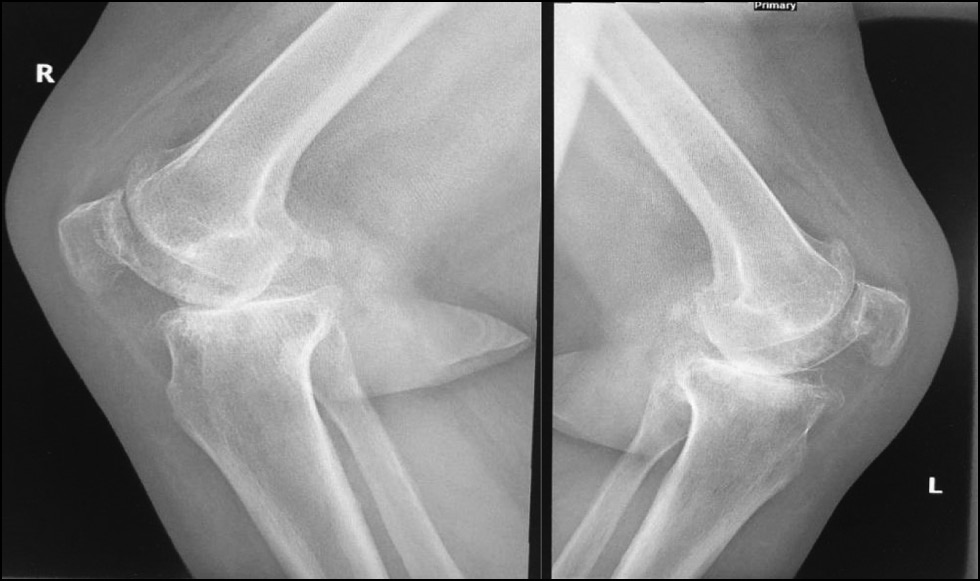

CASE 2. PATIENT 3

Age: 67 years.

Sex: Female.

Diagnosis: Bilateral advanced knee osteoarthritis.

Procedure: Bilateral simultaneous knee arthroplasty.

Associated illnesses: DM and hypertension.

Postoperative follow-up: No postoperative complications were encountered.

Length of hospital stay: 6 days.

Radiological assessment (Fig. 15–18)

Fig. 16. Lateral preoperative x-ray right and left knees showing osteoarthritis.

Рис. 16. Предоперационная боковая рентгенограмма правого и левого колена с признаками остеоартрита.